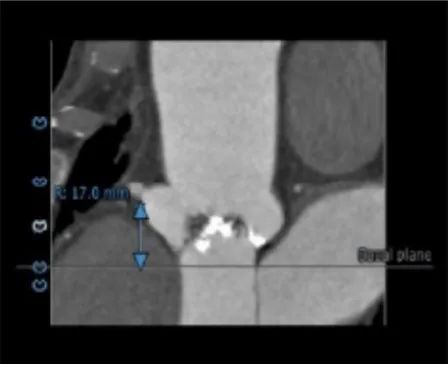

冠脉高度测量:

LEFT CORONARY

左冠开口高度16.0mm

RIGHT CORONARY

右冠开口高度17.0mm